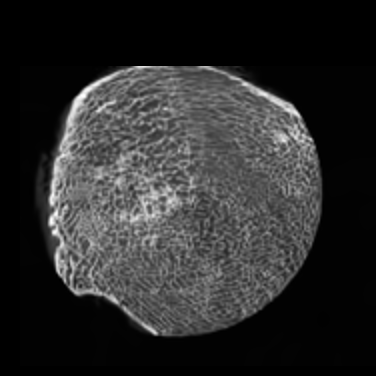

In this study, we used two high-quality sets of training images to demonstrate the fidelity and robustness of the proposed GAN-CIRCLE. As shown in Figs. 4 - 6, these two datasets are of very different characteristics.

III-A1 Tibia dataset

This micro-CT image dataset reflects twenty-five fresh-frozen cadaveric ankle specimens which were removed at mid-tibia from 17 body donors (mean age at death ±plus-or-minus\pm SD: 79.6± 13.2plus-or-minus79.613.279.6\,\pm\,13.2 Y; 999 female). After the soft tissue were removed and the tibia was dislocated from the ankle joint, each specimen was scanned on a Siemens microCAT II (Preclinical Solutions, Knoxville, TN, USA) in the cone beam imaging geometry. The micro-CT parameters are briefly summarized as follows: a tube voltage 100100100 kV, a tube current 200200200 mAs, 720720720 projections over a range of 220220220 degrees, an exposure time of 1.01.01.0 sec per projection, and the filter backprojection (FBP) method was utilized to produce 28.8μm28.8𝜇𝑚28.8~{}\mu m isotropic voxels. Since CT images are not isotropic in each direction, for convenience of our previous analysis [70], we convert micro-CT images to 150μm150𝜇𝑚150~{}\mu m using a windowed sync interpolation method. In this study, the micro-CT images we utilized as HR images were prepared at 150μm150𝜇𝑚150~{}\mu m voxel size, as the target for SR imaging based of the corresponding LR images at 300μm300𝜇𝑚300~{}\mu m voxel size. The full description is in [70]. We target 111X resolution improvement.